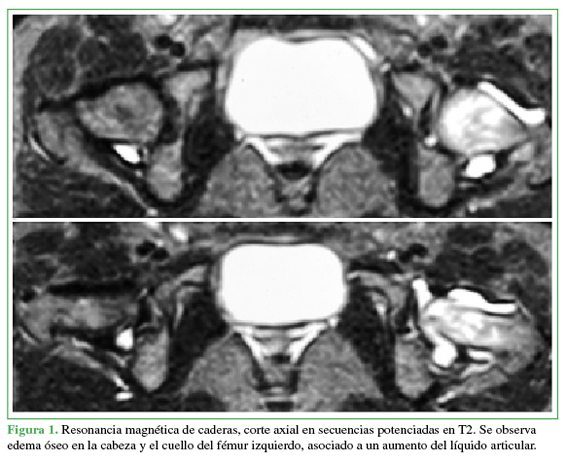

Se presenta un caso de un paciente femenino de 22 años con dolor en cadera izquierda de larga evolución sin antecedentes reelevantes.Descargas